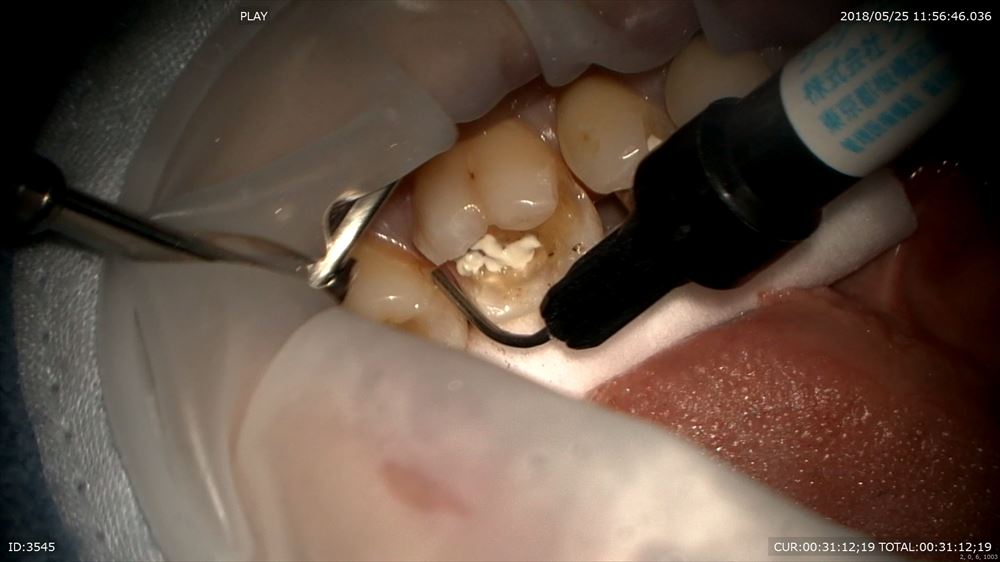

次のケースは左下に違和感があり咬むと痛い

咬むと痛いときはヒビやクラックが原因という事が多いです。金属の下の虫歯だけでなく

実はマイクロスコープを使用してこんな所を観察

ここにも原因があったのです。

ほら。患者さまにもこの画像を見て頂き

ここを拡大。クラック見てみましょう。20倍

この様に虫歯はクラックからも発生します。

クラックの修復。